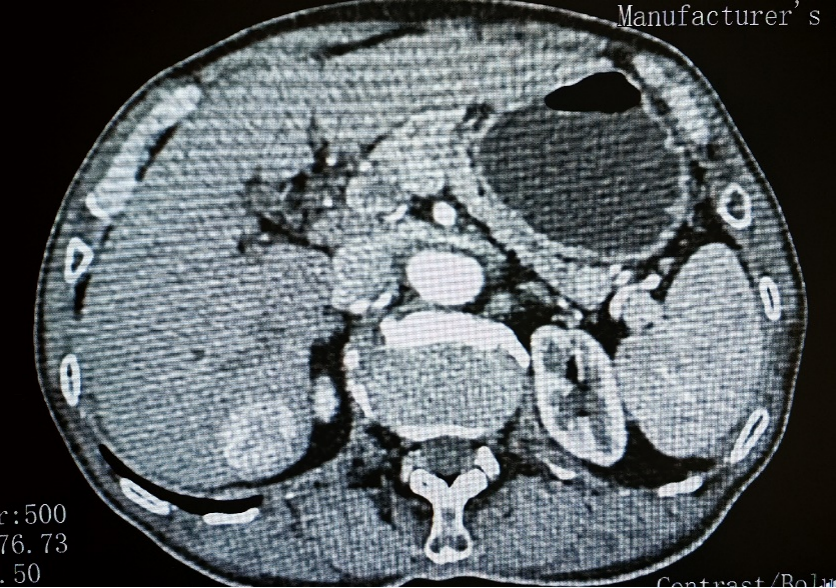

患者有多年乙型肝炎病史,合并腔隙性脑梗塞。除了复杂的基础病,此次入院检查还意外发现肝脏S7段存在一约3.5*3cm占位性病变,经影像学评估考虑为原发性肝癌。

肝脏S7段原发性肝癌影像学表现